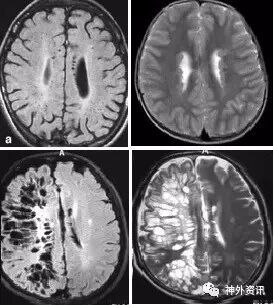

(重要申明:以下每个部分会配磁共振图片,因疾病和影像之间存在同病异象、同像异病,为避免误导,图片不标注疾病,其各自鉴赏,另其中的部分图片来源于网络,有疑问可与本人联系)

如脑梗塞或脑出血等疾病后华勒变性、ALS的锥体束变性等。脑白质疏松症等。

各种肿瘤,如胶质瘤、淋巴瘤、脑膜瘤、血管内淋巴瘤,生殖细胞瘤、各种转移瘤、心房粘液瘤等。神经纤维瘤病也可在中枢出现影像学上类似脱髓鞘的病变。

I--infection,感染